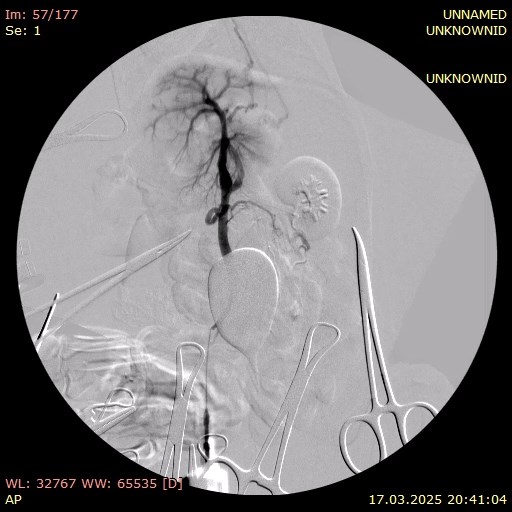

В этот же день пациенту были проведены хирургическое лечение (лапаротомия с аспирацией 800 мл прозрачной жидкости) и портография. Органы брюшной полости расположены анатомически правильно, висцеральный жир умеренно выражен. Сосуды брюшной полости расширены, селезенка умеренно увеличена. Печень значительно уменьшена в размерах, имеет желто-коричневый цвет и сглаженную зернистость. В паренхиме выявлены множественные включения светлого цвета. Желчный пузырь слабо наполнен, мягкий при пальпации. Желудок и кишечник без особенностей, перистальтика выражена хорошо. Измерение давления в портальной вене показало 20 мм вод. ст.

Портография выявила множественные шунты: между портальной веной и каудальной полой веной, а также два спленоазигональных шунта (фото 5).

На основании результатов проведенной лапаротомии и портографии была подтверждена выраженная портальная гипертензия. Для снижения давления в системе воротной вены была выполнена спленэктомия с использованием УЗ-скальпеля. Также была проведена биопсия печени для последующего гистологического исследования.